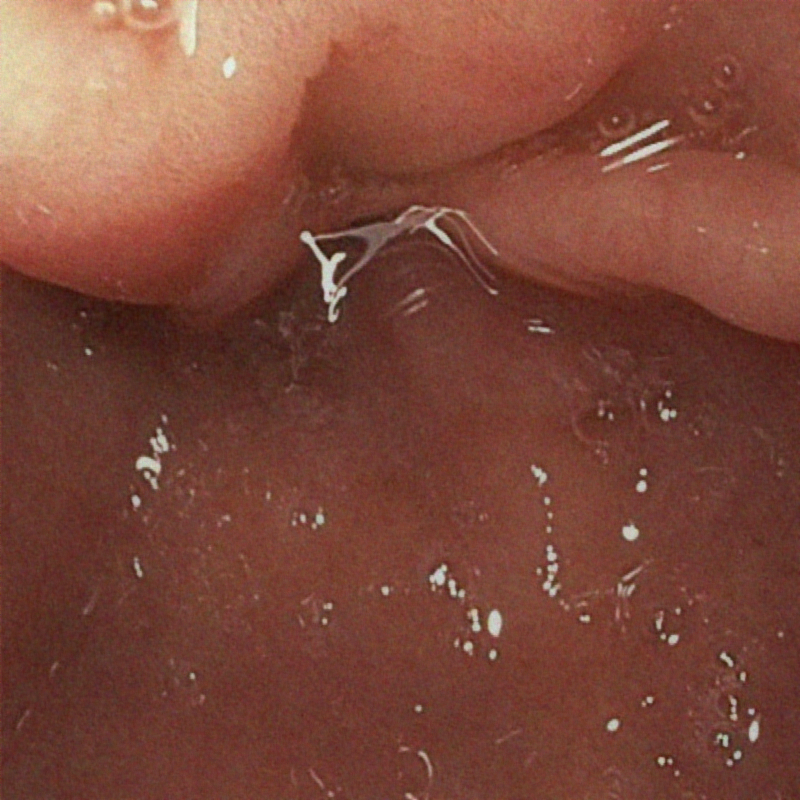

| (a) Input | (b) LIME | (c) HDRNet | (d) LECCM | (e) SwinIR | (f) NAFNet | (g) EndolMLE | (h) Ours | (i) GT |

The proposed method was evaluated on a synthetic dataset. All deep learning-based methods were fine-tuned based on E-kvasri. Figure 2 presents sample results of the proposed method and comparative methods on four endoscopic images from the E-kvasri.